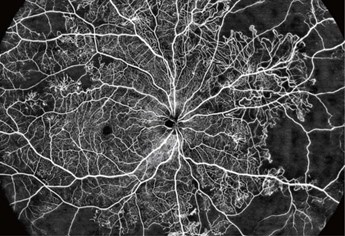

A powerful ophthalmic imaging system that establishes a new benchmark in optical coherence tomography (OCT) and OCT angiography (OCTA). Engineered with an ultra high speed 400 kHz swept source, this device delivers rapid, highly detailed scans of both the anterior and posterior segments of the eye, capturing ultra widefield OCTA images up to 24 × 20 mm in just 7-15 seconds.

Its advanced optics and built in AI algorithms provide precise segmentation, quantification of blood flow, and analysis of retinal curvature and vascular density, offering clinicians comprehensive diagnostic insights in a single acquisition. With high-resolution imaging, robust eye tracking, and an extensive dioptric range, the BMizar improves both routine clinical workflows and the management of complex conditions such as diabetic retinopathy and retinal vascular occlusions. Designed for advanced clinical and research use, it embodies innovation and precision in ophthalmic diagnostics.